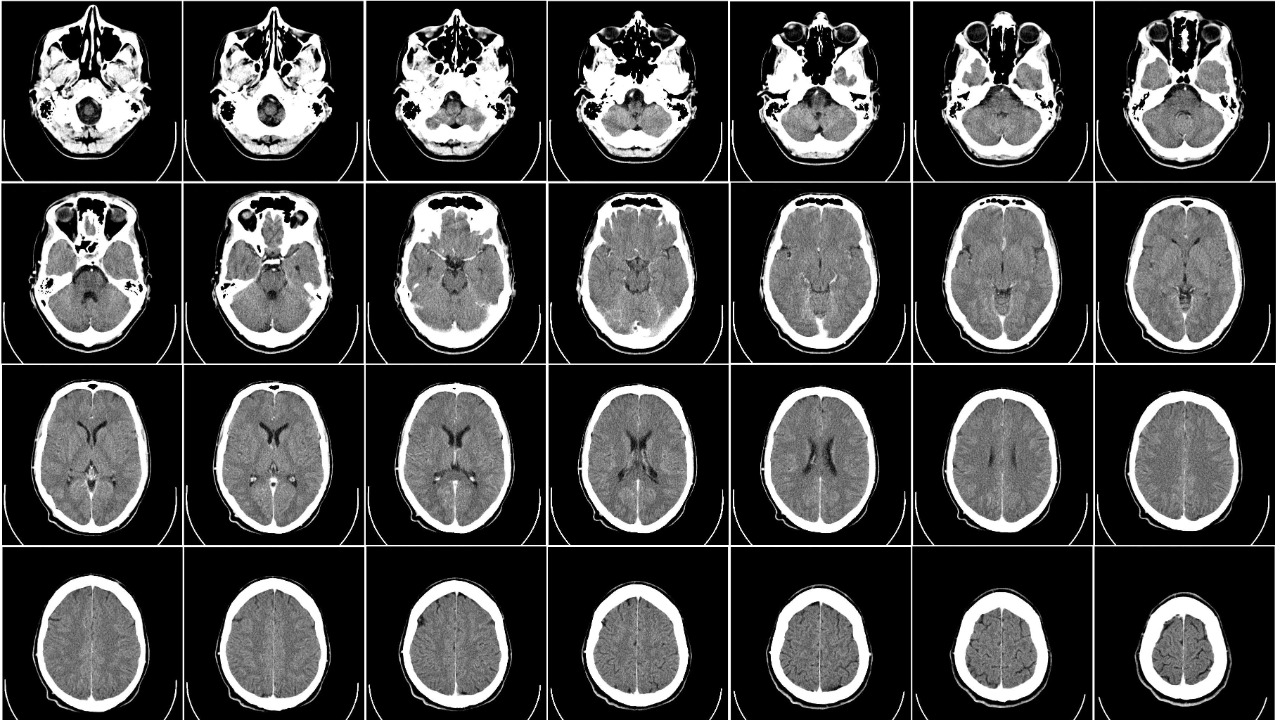

Brain scans have become an invaluable tool in this research. Functional Magnetic Resonance Imaging (fMRI) specifically, is being used to detect memory traces in the brain. By tracking changes in blood flow, fMRI allows scientists to identify areas of the brain that are active during memory formation.

Advanced neuroimaging techniques are also being employed to explore the neural correlations of consciousness. These techniques provide a detailed look at the structure and function of the brain, shedding light on the areas involved in memory retention and consciousness. They are pivotal in understanding how memories might persist in an otherwise unconscious brain.